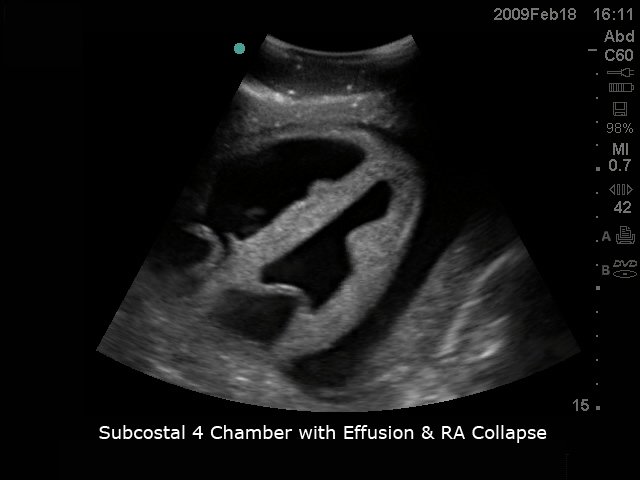

心脏超声训练模型

型号:PC-BP005/PC-BP005.01

模型具有逼真的心脏解剖超声图像,从不同角度可进行经食道和经胸廓心脏20个标准切面探查及测量,同时可进行超声引导下心包穿刺的完整流程训练。